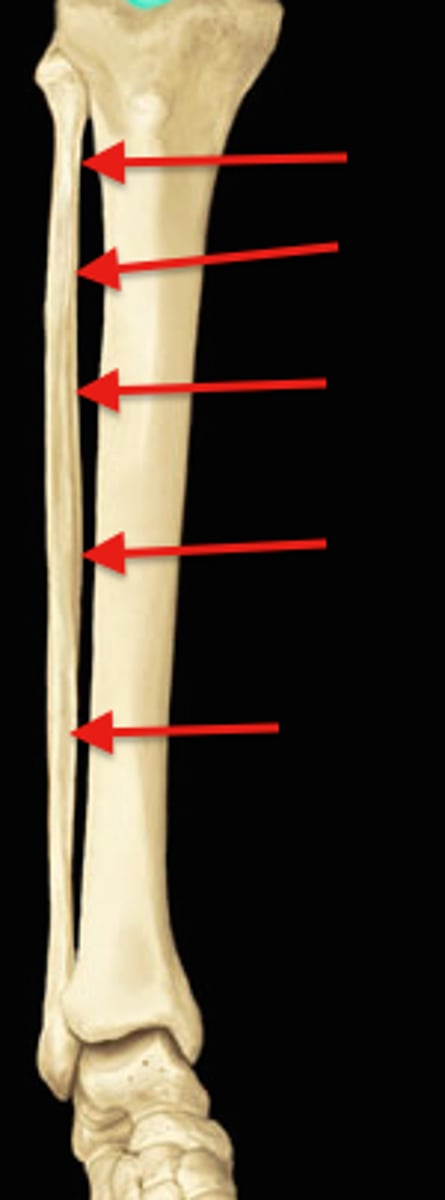

Tibia

Diaphysis/shaft (tibia)

Fibula

Diaphysis/shaft (fibula)

Medial border for interosseous membrane